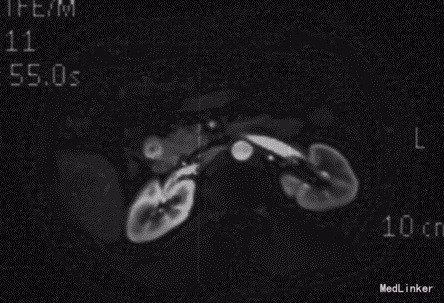

查体:神清,腹软,未及包块,无压痛及反跳痛,神经系统检查未见异常 辅查:外院头颅CT平扫:腔隙性脑梗;胰腺CT平扫:胰头、十二指肠降部稍低密度影,肝内多发小囊肿;上腹部增强CT:胰腺低密度影,考虑良性;肝内多发小囊肿。 入院检查:血、尿、粪常规、肝肾功能、电解质、凝血功能正常;AFP、CEA、CA19-9、CA125、CA15-3、CA72-4均正常;胰岛素78.33mIU/L,C肽 4.91ug/L。腹腔动脉DSA:胰头区富血供肿瘤; 胰腺增强MRI:1、胰头部富血供病变,考虑胰岛素瘤可能性大;2、肝内多发小囊肿。